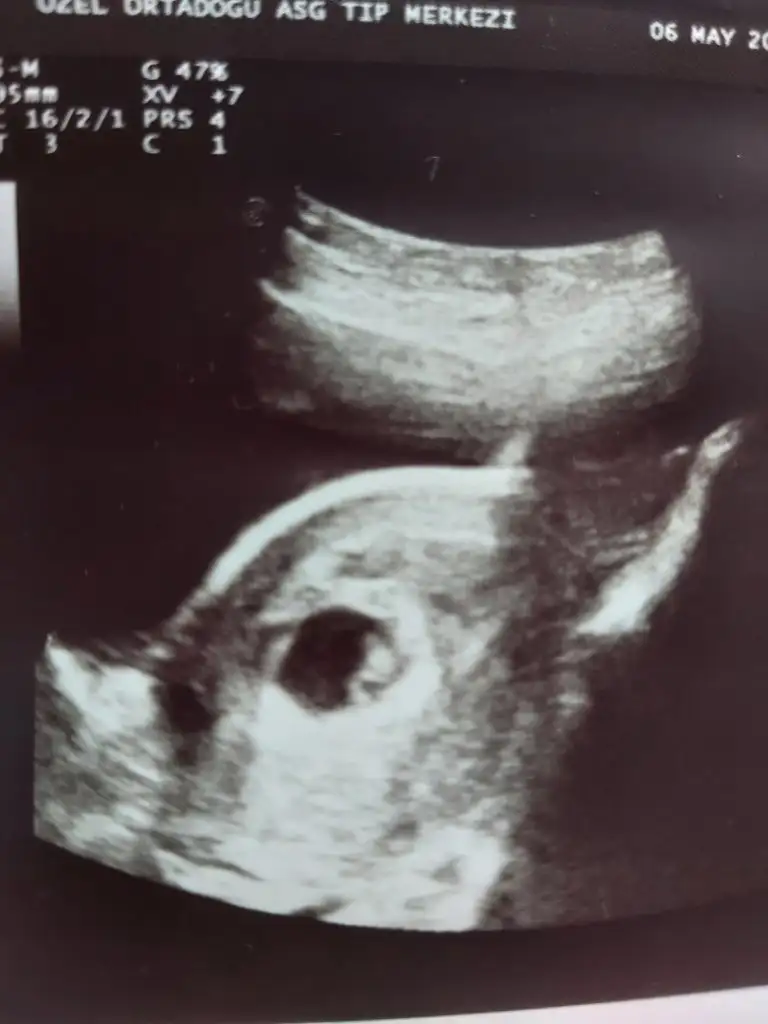

Canim kıza benzettim ama hiç emin değilim sen ne hissediyosunBir de bu ultrason görüntüsüne bakabilirmisiniz

Canim kıza benzettim ama hiç emin değilim sen ne hissediyosun

Canım plesantan sağda karından ultrasonsa eğer kıza benziyoEki Görüntüle 3071532 banada bir yorum lütfen